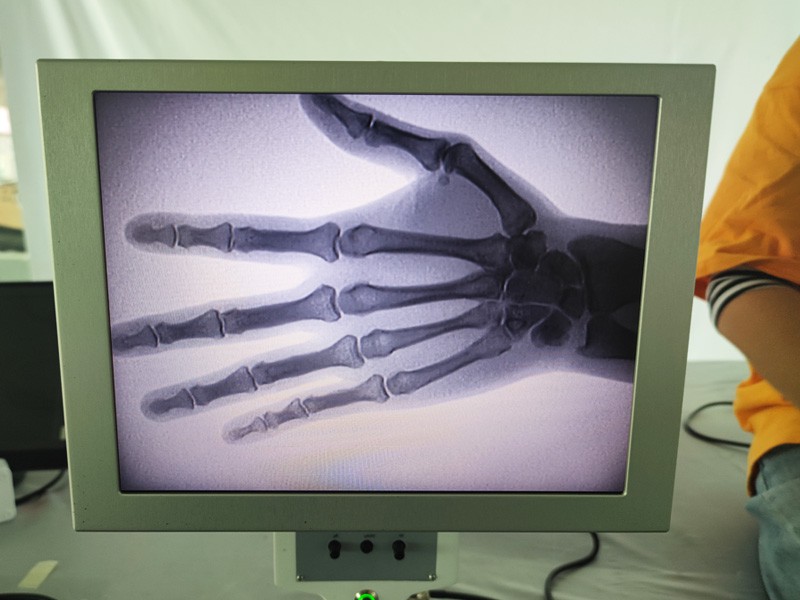

A hordozható röntgenkészülék beépített kijelzővel rendelkezik, a kezelő a megjelenített képet valós időben tekintheti meg a kijelzőnek megfelelően. A kép zárolható és megfigyelhető a kijelzőn keresztül. Speciális védőlemezzel van felszerelve a kezelők védelmére. Rotációs kártyával nagyon kényelmes felszerelni. Alkalmas orvosi, kisállat-, ipari és elektronikai termékgyártók, ellenőrző és karbantartó részlegek, valamint tudományos kutatólaboratóriumok számára a legjobb röntgenvizsgáló berendezések és megoldások biztosítására.

A X-ray of Extremities rendszer egy speciális radiográfiai rendszer, amelyet a végtagok csontjairól és ízületeiről készítenek, beleértve a karokat, lábakat, kezeket és lábfejeket. A rendszert úgy tervezték, hogy tiszta és pontos képet adjon a végtagok csontjairól és ízületeiről diagnosztikai célokra. A berendezés sokoldalú, könnyen használható, és számos ortopédiai és sportorvosi állapot diagnosztizálására használható.

3. Gyors és egyszerű használat: A X-ray of Extremities berendezés felhasználóbarát és egyszerűen kezelhető. Az orvosok és a személyzet gyorsan készíthet képeket, csökkentve ezzel a betegek várakozási idejét.